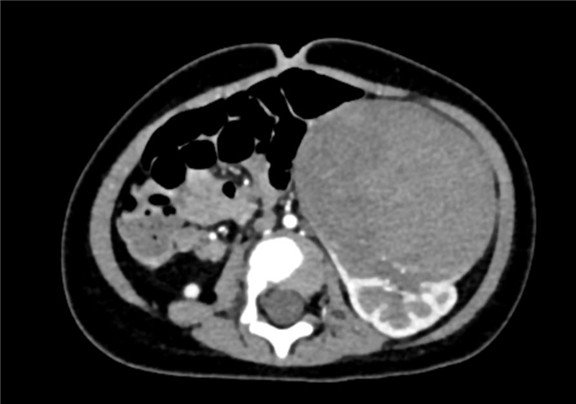

上腹部增强CT:左肾巨大占位性病变,疑似肾母细胞瘤

术前CT检查:

动脉期

静脉期

平衡期